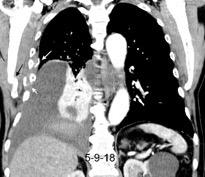

Síndrome de afectación postcardiaca (postcardiac injury)

Post infarto 1-7 % (Dressler)

Trauma cerrado Implantación marcapasos

Cirugía cardiaca. 17-31% (Post.pericardiotomía)

3707 pacientes 29 Derrames (0,78%) > de 25% del hemitórax

Todas menos 2 Izdos.

Angioplastia

By-pass coronario 21-10-03